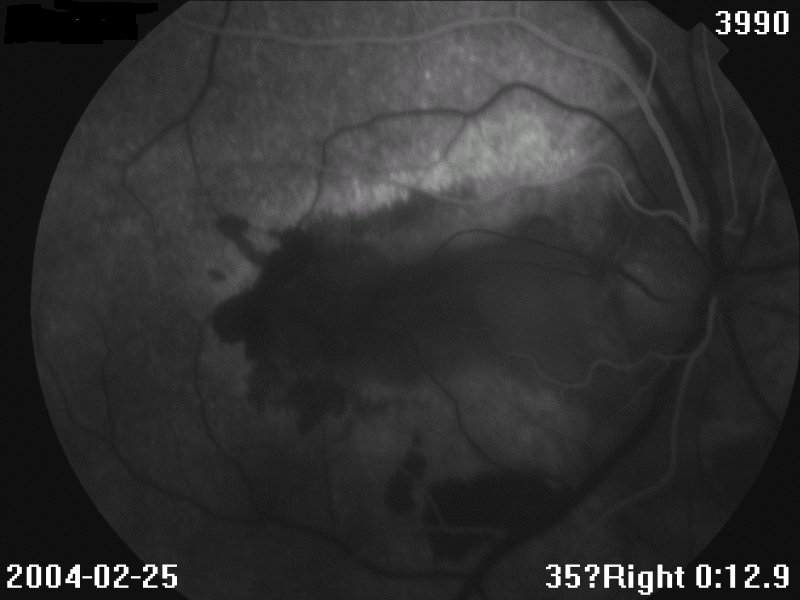

眼底见:玻璃体尘状混浊 眼底图 右眼 左眼 荧光造影图 眼科B超 OCT 视野 讨论: 1、诊断及鉴别诊断

2、眼底见病灶起自视乳头,葡行性发展,呈地图状,界清

3、有CNV,表现为网膜下出血、渗出

4、FFA:早期低荧光,晚期高荧光;有荧光渗漏(CNV)、遮挡荧光(出血)

FFA:早期低荧光,晚期高荧光;如有CNV,可见荧光渗漏,或出血遮挡荧光。晚期病例:病灶边缘高荧光,中央低荧光,经常见大的脉络膜血管

ICGA:活动病灶为低荧光,脉络膜血管梗塞或渗出、水肿遮挡荧光